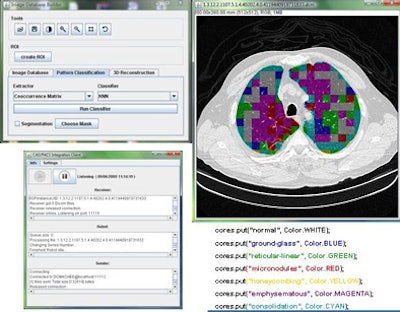

The CAD pipeline component performs five separate steps: preprocessing, segmentation, feature extraction, classification, and postprocessing, Mazzoncini de Azevedo-Marques said.

The preprocessing step extracts images from the DICOM files. Segmentation divides the images into regions of interest (ROI) of 20 x 20 pixels each. The classification step uses a KNN classifier to categorize each ROI into one of the nine patterns.

Two of the nine classes, background and outside tissue, indicate regions outside the lungs. The remaining seven classes refer to patterns found in the lungs: normal parenchyma, ground-glass opacities, reticular and linear opacities, nodular opacities, honeycombing, emphysematous change, and consolidation.

| Graphic user interface of image-processing pipeline (implemented in Java) that performs five separate steps: preprocessing, segmentation, feature extraction, classification, and postprocessing. |

In the last step, postprocessing, each pattern type is assigned a color label and the DICOM file is rebuilt. The communication/archiving agent finishes off the process by including the image slices with the labeled ROIs as a new image series in the exam and sending it back to the PACS server. The color coding allows radiologists to easily see which lung regions might be affected by a particular type of diffuse lung disease.

The CAD pipeline component also uses Java, according to Mazzoncini de Azevedo-Marques. A classification algorithm extracts features from each ROI using values calculated from co-occurrence matrices (energy, contrast, correlation, entropy) obtained for four directions: horizontal, vertical, two diagonal levels, and one level of Daubechies wavelets (for energy and entropy).